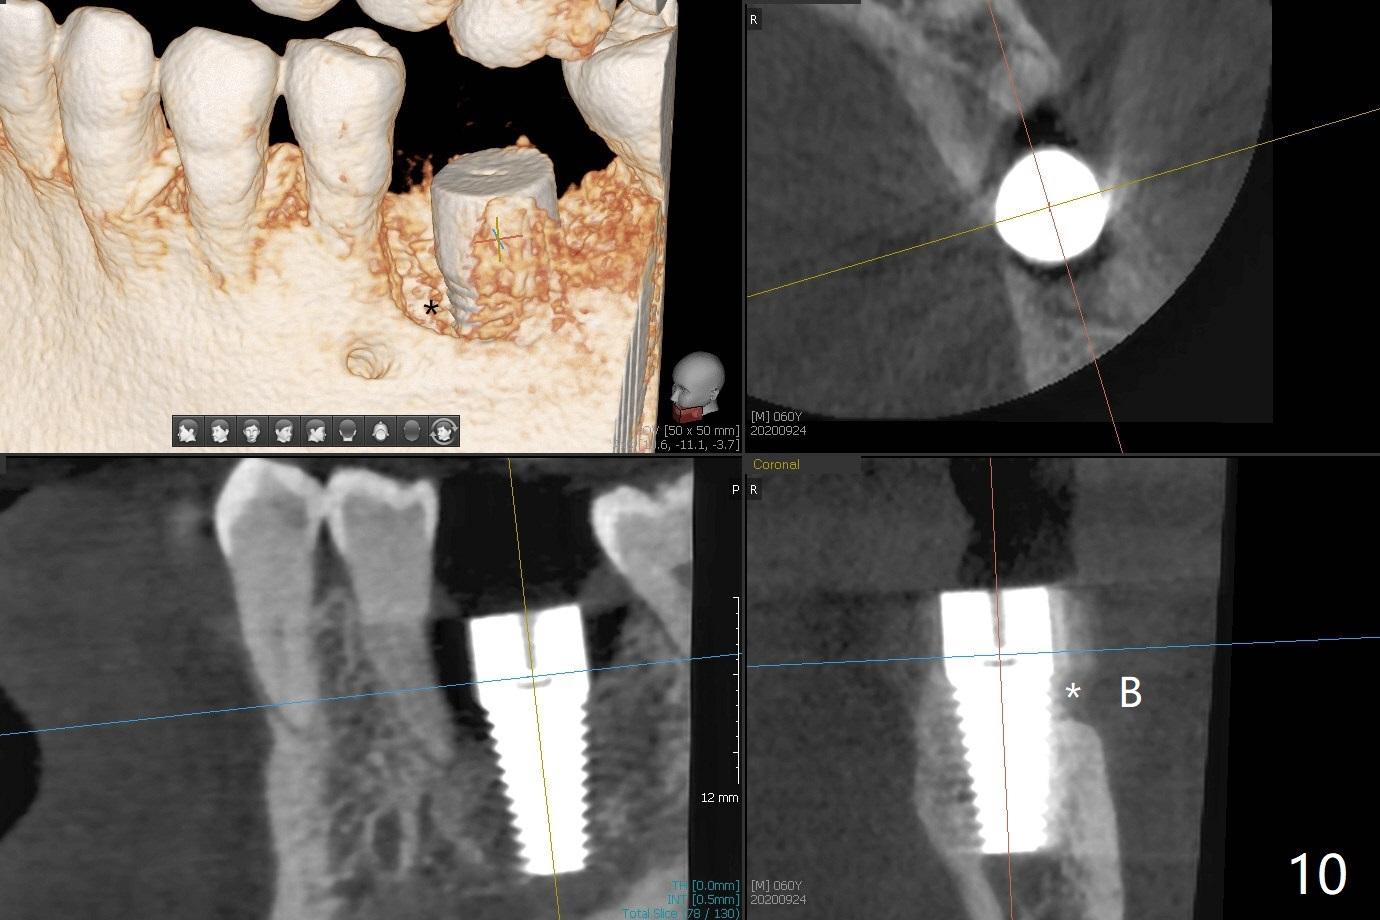

After 4.0x10 mm drill with 9 mm offset for 4.5x10 mm bone-level implant at #19, a 4.5x17 mm tissue level tap is inserted with apparently low torque (probably without reaching the depth). When a 4.5x14 mm tissue level implant is placed with high torque, a 4.5x7.3 mm drill is used for ~ 6.5 mm. The implant loses the primary stability with over-insertion (Fig.1). When an abutment is placed, the implant is critically loose. Mixture of autogenous bone, Osteogen and allograft is placed in the osteotomy. The implant regains stability with better placement level for restoration (Fig.2). In fact the bone density around the implant increases (Fig.2 *). For the first 7 days postop, the patient has to take Advil. When he returns for follow up 8 days postop (Fig.3), the pain decreases, while there is minor degree of lower lip paresthesia. Medrol Dose Pak and Tylenol III are prescribed. The implant is loose 24 days postop; after removal of the implant and apparently infected bone graft, a 7x14 mm dummy implant is inserted with <20 Ncm and 3-4 mm clearance (Fig.4). A longer dummy implant seems to improve stability (Fig.5). So does the definitive implant (Fig.6,7, 25 Ncm), but it is placed low. The gingiva looks healthy 13 days postop (2nd placement). A healing cap will be placed for restoration ~ 3 months postop. CT will be taken if the implant needs to be backed up to determine whether there is enough bone buccolingually. Due to coronavirus and prolonged placement of a healing abutment with poor oral hygiene, the buccal gingiva of the implant is erythematous 1 year postop (Fig.8 healing cap just removed) with bone loss (Fig.9,10 *). Sticky bone seems to be necessary. A 6x5 mm abutment with slots will be placed to hold periodontal dressing in place.